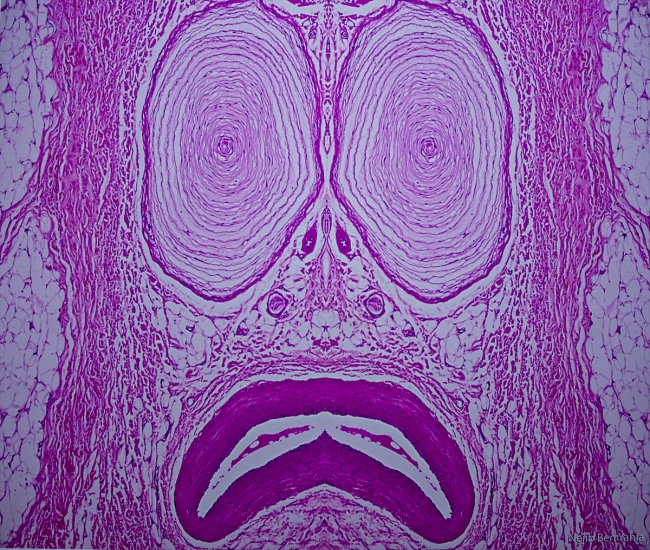

Mikroskop altında büyütülen organizmalarda kimi zaman kelebek, kimi zaman gülen yüz, kimi zaman da balık görüntüsü yakalayan patologların eserleri, Çankaya Belediyesi Çağdaş Sanatlar Merkezinde sergileniyor.

Patoloji Dernekleri Federasyonunun 2 yıldır gerçekleştirdiği, uluslararası katılımlı yarışmada ödül alan ve sergilenmeye değer bulunan mikrofotografik görüntülerden oluşan Pathart Sergisi, insan dokusuna farklı ve estetik bir bakış açısı getiriyor.

Bilimle sanatı buluşturmak için yola çıkan patologlar, mikroskoptan objektife sihirli görüntüler yansıtıyor.

Mikroskop altında gördükleri farklı imgeleri ya da renk ahengini fotoğrafladıklarını vurgulayan Usubütün, "Aslında buraya yansıttıklarımız günlük hayatımızda birebir gördüklerimiz değil, yorumladıklarımız. Biz daha sıkıcı işlerle uğraşıyoruz. Onları biraz renklendirmek için dokuların içinde kelebekler, ördekler bulduk ya da bunları başka objelere benzettik" dedi.